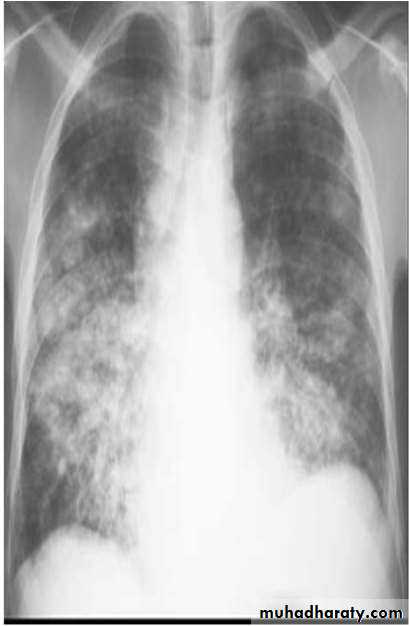

Chest X-ray and UltrasoundLobar pneumonia

• Patchy opacification ,consolidation.

• Air bronchogram (air-filled bronchi appear lucent against

consolidated lung tissue)

Bronchopneumonia

• Typically patchy and segmental shadowing

• X Ray

• Homogenous opacity with air bronchogram

• LOBAR PNEUMONIA

• Peripheral airspace consolidation pneumonia• Without prominent involvement of the bronchial tree

• RUL Consolidation

• RML Consolidation

• RLL Consolidation

• BRONCHOPNEUMONIA

• Centrilobular and Peribronchiolar opacity pneumonia• Tends to be multifocal

• Patchy in distribution rather than localized to any

• one lung region